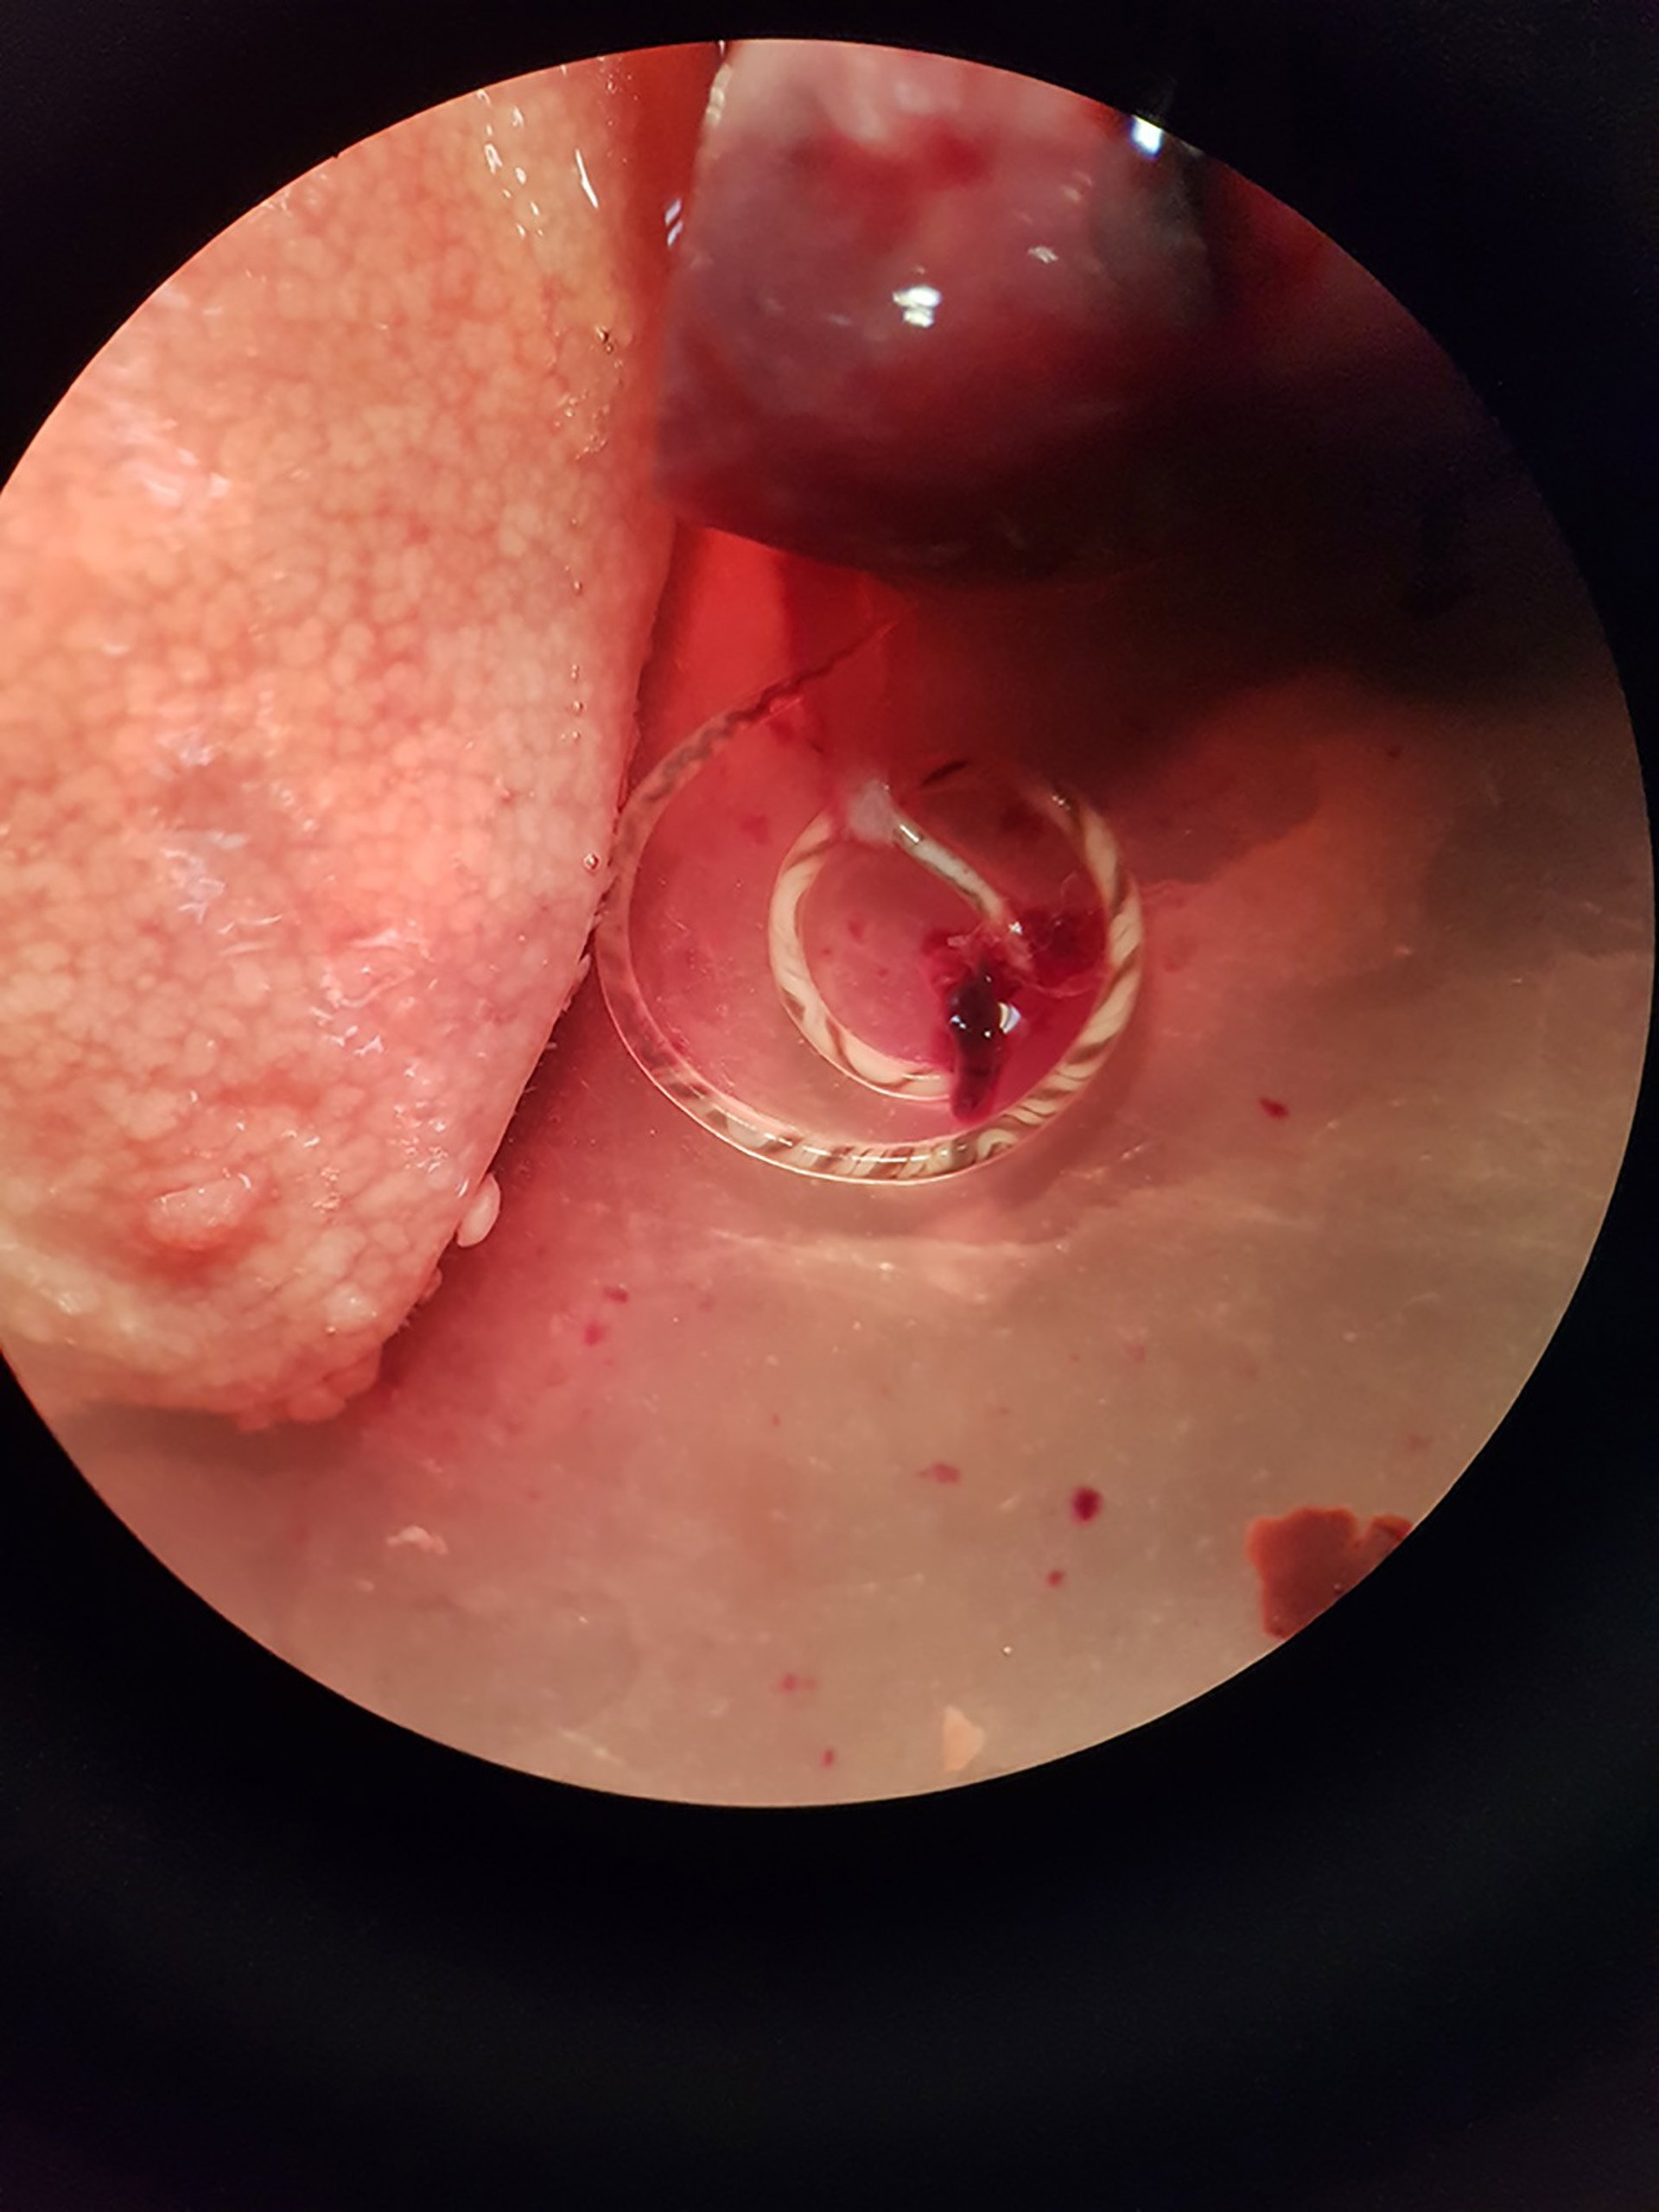

Una investigación liderada por el grupo Parásitos y Salud de la Universitat de Valncia (UV) ha hallado por primera vez en Europa continental el nematodo (gusano) Angiostrongylus cantonensis, un parásito zoonótico capaz de ser transmitido al ser humano que está presente en las arterias pulmonares de las ratas y que es el agente causal más común en el ser humano de la meningitis eosinofílica (ME).

En concreto, el parásito se ha localizado en dos especies de ratas de la ciudad de Valncia. Esta enfermedad provoca una inflamación de la membrana que cubre el cerebro y puede causar ataques, lesiones cerebrales y trastornos visuales, entre otros síntomas.